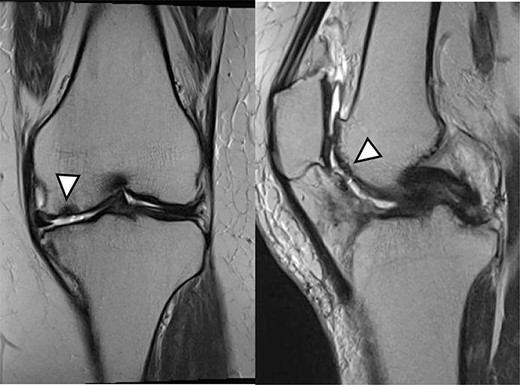

There were cartilage defects (arrowhead) in the medial femoral condyle and trochlea of the left knee (a, b).

Articular cartilage injury was shown in the medial femoral condyle (arrowhead) (2.5 × 3.5 cm; Outerbridge classification, Grade III) and trochlea (arrowhead) (1.3 × 1.7 cm; Outerbridge classification, Grade III) (a, b).

A 42-year-old female (BMI, 27.4 kg/m2) presented with 2 years of left knee medial joint pain. Active range of motion (ROM) in the left knee was from 0 to 140 degrees with no extension lag. Preoperative Tegner scores, Lysholm scores and Knee Injury and Osteoarthritis Outcome (KOOS) scores are shown in Table 1. Preoperative radiographs of the left knee joint showed mild medial osteoarthritis (OA) of the knee and hip–knee–ankle (HKA) angle of 1.5-degree varus. 1.5-Tesla MRI was performed on unit (Toshiba, Kawasaki, Japan) was used with an extremity surface coil. Proton density images were obtained using the fast spin-echo technique. A modified magnetic resonance observation of cartilage repair tissue (MOCART) system was used for the quantitative evaluation of MRI findings of the cartilage injury [15–17]. MRI showed cartilage injury of the medial femoral condyle (MFC) and trochlea of the left knee (Fig. 1).

MRI showed cartilage injury of the medial femoral condyle (arrowhead).